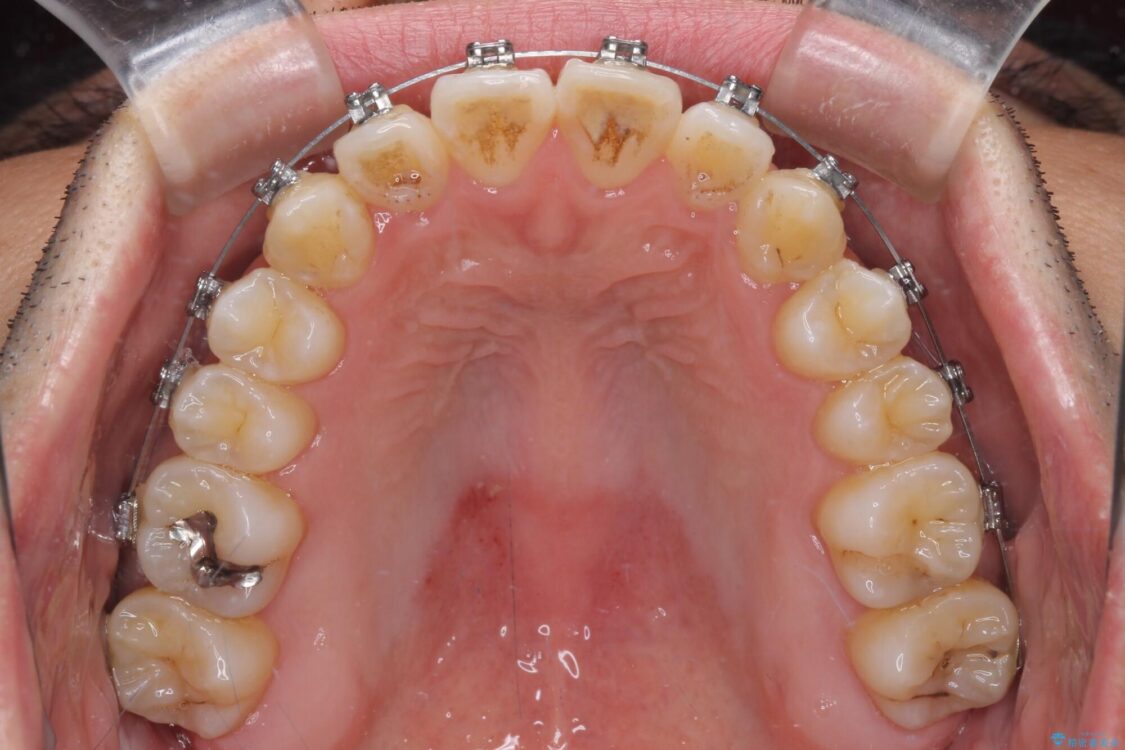

治療前

• 左右の八重歯が気になる ワイヤー装置での咬み合わせ改善 治療前画像